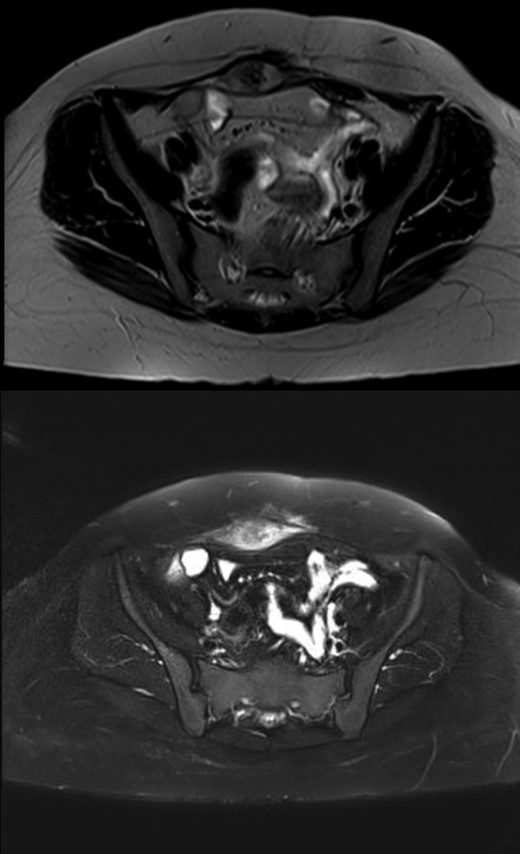

She was followed up with biannual MRI’s with no recurrence. Two years later, the patient noticed a growing mass. The follow-up MRI revealed development of a well-defined oval-shaped soft tissue lesion at the site of the previously resected anterior abdominal wall desmoid tumor measuring 4.3 × 2 cm, heterogeneously hypertense on T2, hypointense on T1 and significant enhancement on the delayed post contrast images, in keeping with a recurrent desmoid tumor (Fig. 1). Following the MRI, the patient was referred to our institution.

MRI images demonstrating the recurrent abdominal wall desmoid tumor located in the right lower abdomen, which is heterogeneously hypertense on T2 and hypointense on T1.